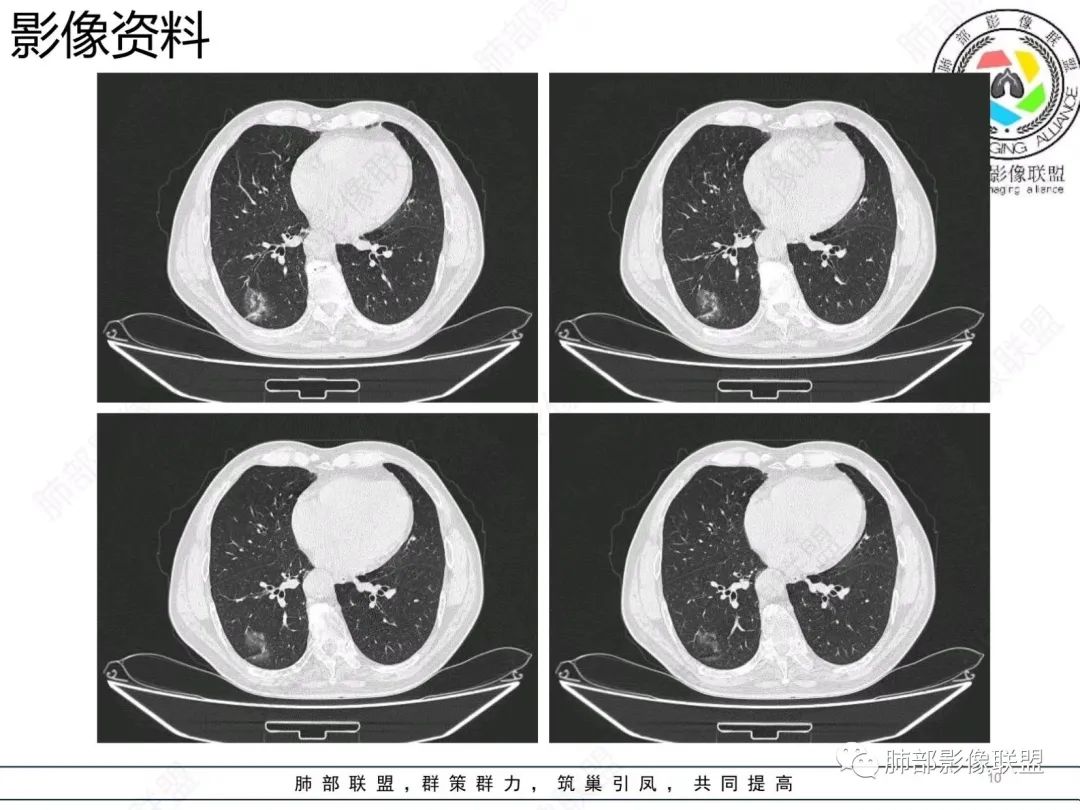

【病例】胸膜下的混合密度结节—良恶之争

老年男性,右肺下叶混合磨玻璃密度结节,可见血管弯征,首先考虑肺腺癌。

右肺下叶背段不规则结节,边界欠清,可见少许晕征,另见胸膜凹陷征及血管弯,考虑腺癌,鉴别隐球菌。

右肺下早不规则结节,周围少许磨玻璃晕,胸膜有牵拉凹陷,虽然部分边界平直,但血管受牵拉弯曲,首先还是考虑肿瘤,腺癌

右肺下叶背段斑片影,边缘平直、局部膨隆,可见磨玻璃密度影,界清,胸膜牵拉,良恶性需要进一步鉴别,倾向隐球,鉴别粘液腺癌。

老年男性,右肺下叶胸膜下结节,边缘见清晰磨玻璃密度影及少许索条,支气管进入后截断,周围血管弯,考虑腺癌,鉴别隐球菌

右肺下叶胸膜下混合密度结节,分叶、毛刺,磨玻璃边界尚清晰,血管集束,支气管进入阻断,考虑腺癌

右肺下叶背段胸膜下肿块,边缘不规则,分叶,毛刺,有磨玻璃,边界清,近肺门侧见血管聚集,支气管进入后闭塞,右肺下叶肺静脉牵拉扭曲。诊断,支持腺癌

老年患者,无呼吸道相关症状,肺部影像学表现:胸膜下占位,有结节融合趋势,内有低密度灶。考虑隐球菌,鉴别腺癌。

胸膜下结节,与胸膜平行,多结节融合,边缘模糊,直边征,考虑炎性肉芽肿,隐球,腺癌

右肺下叶背段实性结节,边缘分叶,较平直,长轴平行胸膜,胸膜增厚,考虑炎性假瘤,隐球菌,鉴别腺癌。

混合性磨玻璃结节,边界清晰,血管打弯,考虑腺癌,鉴别炎性肉芽肿病变。

老年男性,体检发现,无症状,右肺下叶背段肿块影,边缘清楚,无卫星灶,棘状突起,毛刺征,血管集支束,空泡征,考虑恶性肿瘤。

老年男性,体检发现。右肺下叶混合磨玻璃结节,渗漏征,短毛刺,血管集支束,空泡,考虑腺癌。

老年男性右肺下叶靠近胸膜一不规则混合密度影,周围有渗出,内见支气管扩张,考虑炎性病变隐球鉴别腺癌

老年男性 右肺下叶胸膜下见一团状实性病灶+边缘磨玻璃,边缘形态不规则,,局部有平直,长轴平行于胸膜面,整体收缩力偏弱,邻近胸膜面轻度增厚,纵隔窗显示病灶内可见支气管充气,考虑炎性肉芽肿,隐球菌可能,鉴别黏液腺癌。

右肺下叶实行病灶,边缘部分有边界清晰的磨玻璃影,实变明显层面,可见平直。考虑腺癌

右下肺近胸膜病变,周围可见磨玻璃影,界限无法判断清楚?模糊?。考虑右下肺占位:真菌感染?腺癌?淋巴瘤?

右肺下叶胸膜下结节,边界清楚毛玻璃,有分叶、毛刺、血管集束及胸膜增厚,考虑肉芽肿性病变,鉴别于腺癌

右肺下叶实性病灶,局部平直,考虑炎性病变,隐球菌可能

胸膜下结节,长轴与胸膜平行,边缘模糊,直边征胸膜凹陷牵拉不明显,考虑炎性肉芽肿,隐?鉴别腺癌。

右肺下叶后基底段胸膜下斑块影,边缘清楚,有平直和膨隆特点,周围清楚GGO,较模糊(似清非清,邻近见多发纯GGO结节,以肺腺泡分布,主体病灶与胸膜平行,收缩力弱,边缘见支气管充气征,首诊断炎性肉芽肿,抗炎治疗和查下隐球荚膜抗原两方面进行,另取旧片对比,与粘液腺Ca鉴别,最后经皮肺穿刺病理诊断!

上面这些征象存在炎性病变可能,我先考虑炎性病变——隐球,这样的血管弯在肺隐球菌病里也出现过。腺癌尤其是粘液腺癌也不敢排除。建议完善血隐球菌荚膜抗原、经皮肺穿刺活检等检查。

结节型粘液腺癌,具有血管弯,支气管截断,磨玻璃边界清楚等恶性征象,同时磨玻璃内部较糊,似清非清,不符合普通腺癌附壁生长特点,更像局限的粘液成分。收缩力不强,胸膜局部微积液,内部小空洞(考虑局部粘液排除形成),所以考虑结节型粘液腺癌。